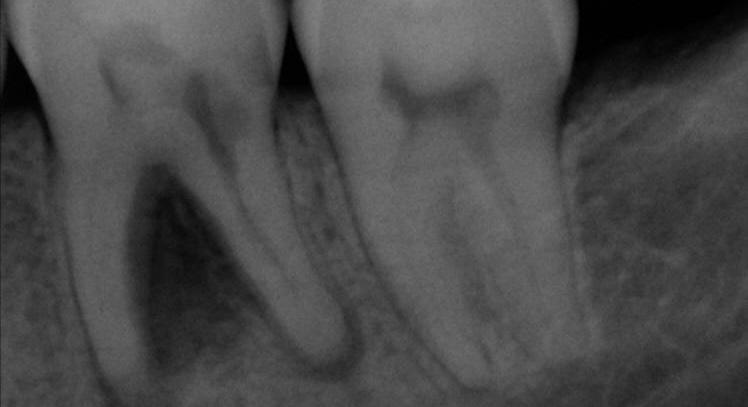

Case 1: 46 years old Male patient, ASA 1, presented for the evaluation and the treatment of tooth #36. On clinical examination the tooth was sensitive to percussion and palpation. The radiographic examination showed a very large radiolucency on both mesial and distal roots, a separated instrument in the mesio-lingual canal. The diagnosis of previously initiated with symptomatic apical periodontitis was made, and the endodontic treatment was indicated.

Following aesthesia and rubber dam placement, access was performed, and canals were located. The coreonal fragment was removed and the apical fragment was bypassed. The canals were instrumented using Edge endo X7 files (EdgeEndo) to size 35.04 in the mesial canals and 40.04 in the distal canal.

Canals were obturated using hydraulic condensation using EdgeBioCeramic Sealer (EdgeEndo). Bioceramic cement was used for its antibacterial and bioactive properties. The one year follow up shows a complete healing of the lesion.